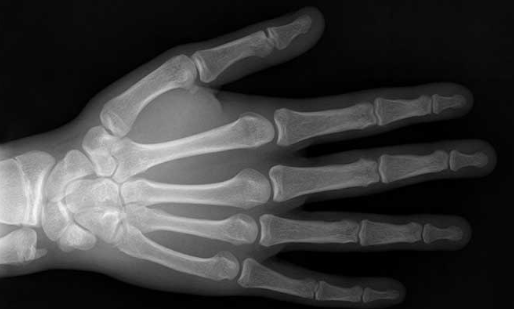

Röntgen repetiu o experimento por diversas vezes, aumentando a distância entre a placa e o tubo, e também colocando diferentes objetos entre eles. Ao segurar esses objetos, ele viu os ossos de sua mão projetados na tela. Com isso, ele concluiu que o tubo com o qual estava trabalhando emitia algum tipo ainda desconhecido de radiação capaz de atravessar o corpo humano. Por não saber do que se tratava, ele chamou essa radiação de Raios X, sendo X a incógnita da matemática.

Como sabia que havia descoberto algo interessante, mas não tinha certeza dos resultados de seus experimentos, Röntgen trabalhou isolado e em segredo por algum tempo em seu laboratório, onde comia e dormia. Além disso, substituiu a tela que usava por uma chapa fotográfica e convenceu sua esposa a participar de seus experimentos. Após imobilizar a mão da esposa sobre um filme fotográfico, ligar o tubo por quinze minutos e revelar o filme, Röntgen observou a imagem dos ossos e do anel que ela usava, além de uma penumbra relativa aos tecidos moles, que por serem mais permeáveis aos raios, produziam uma sombra mais fraca.